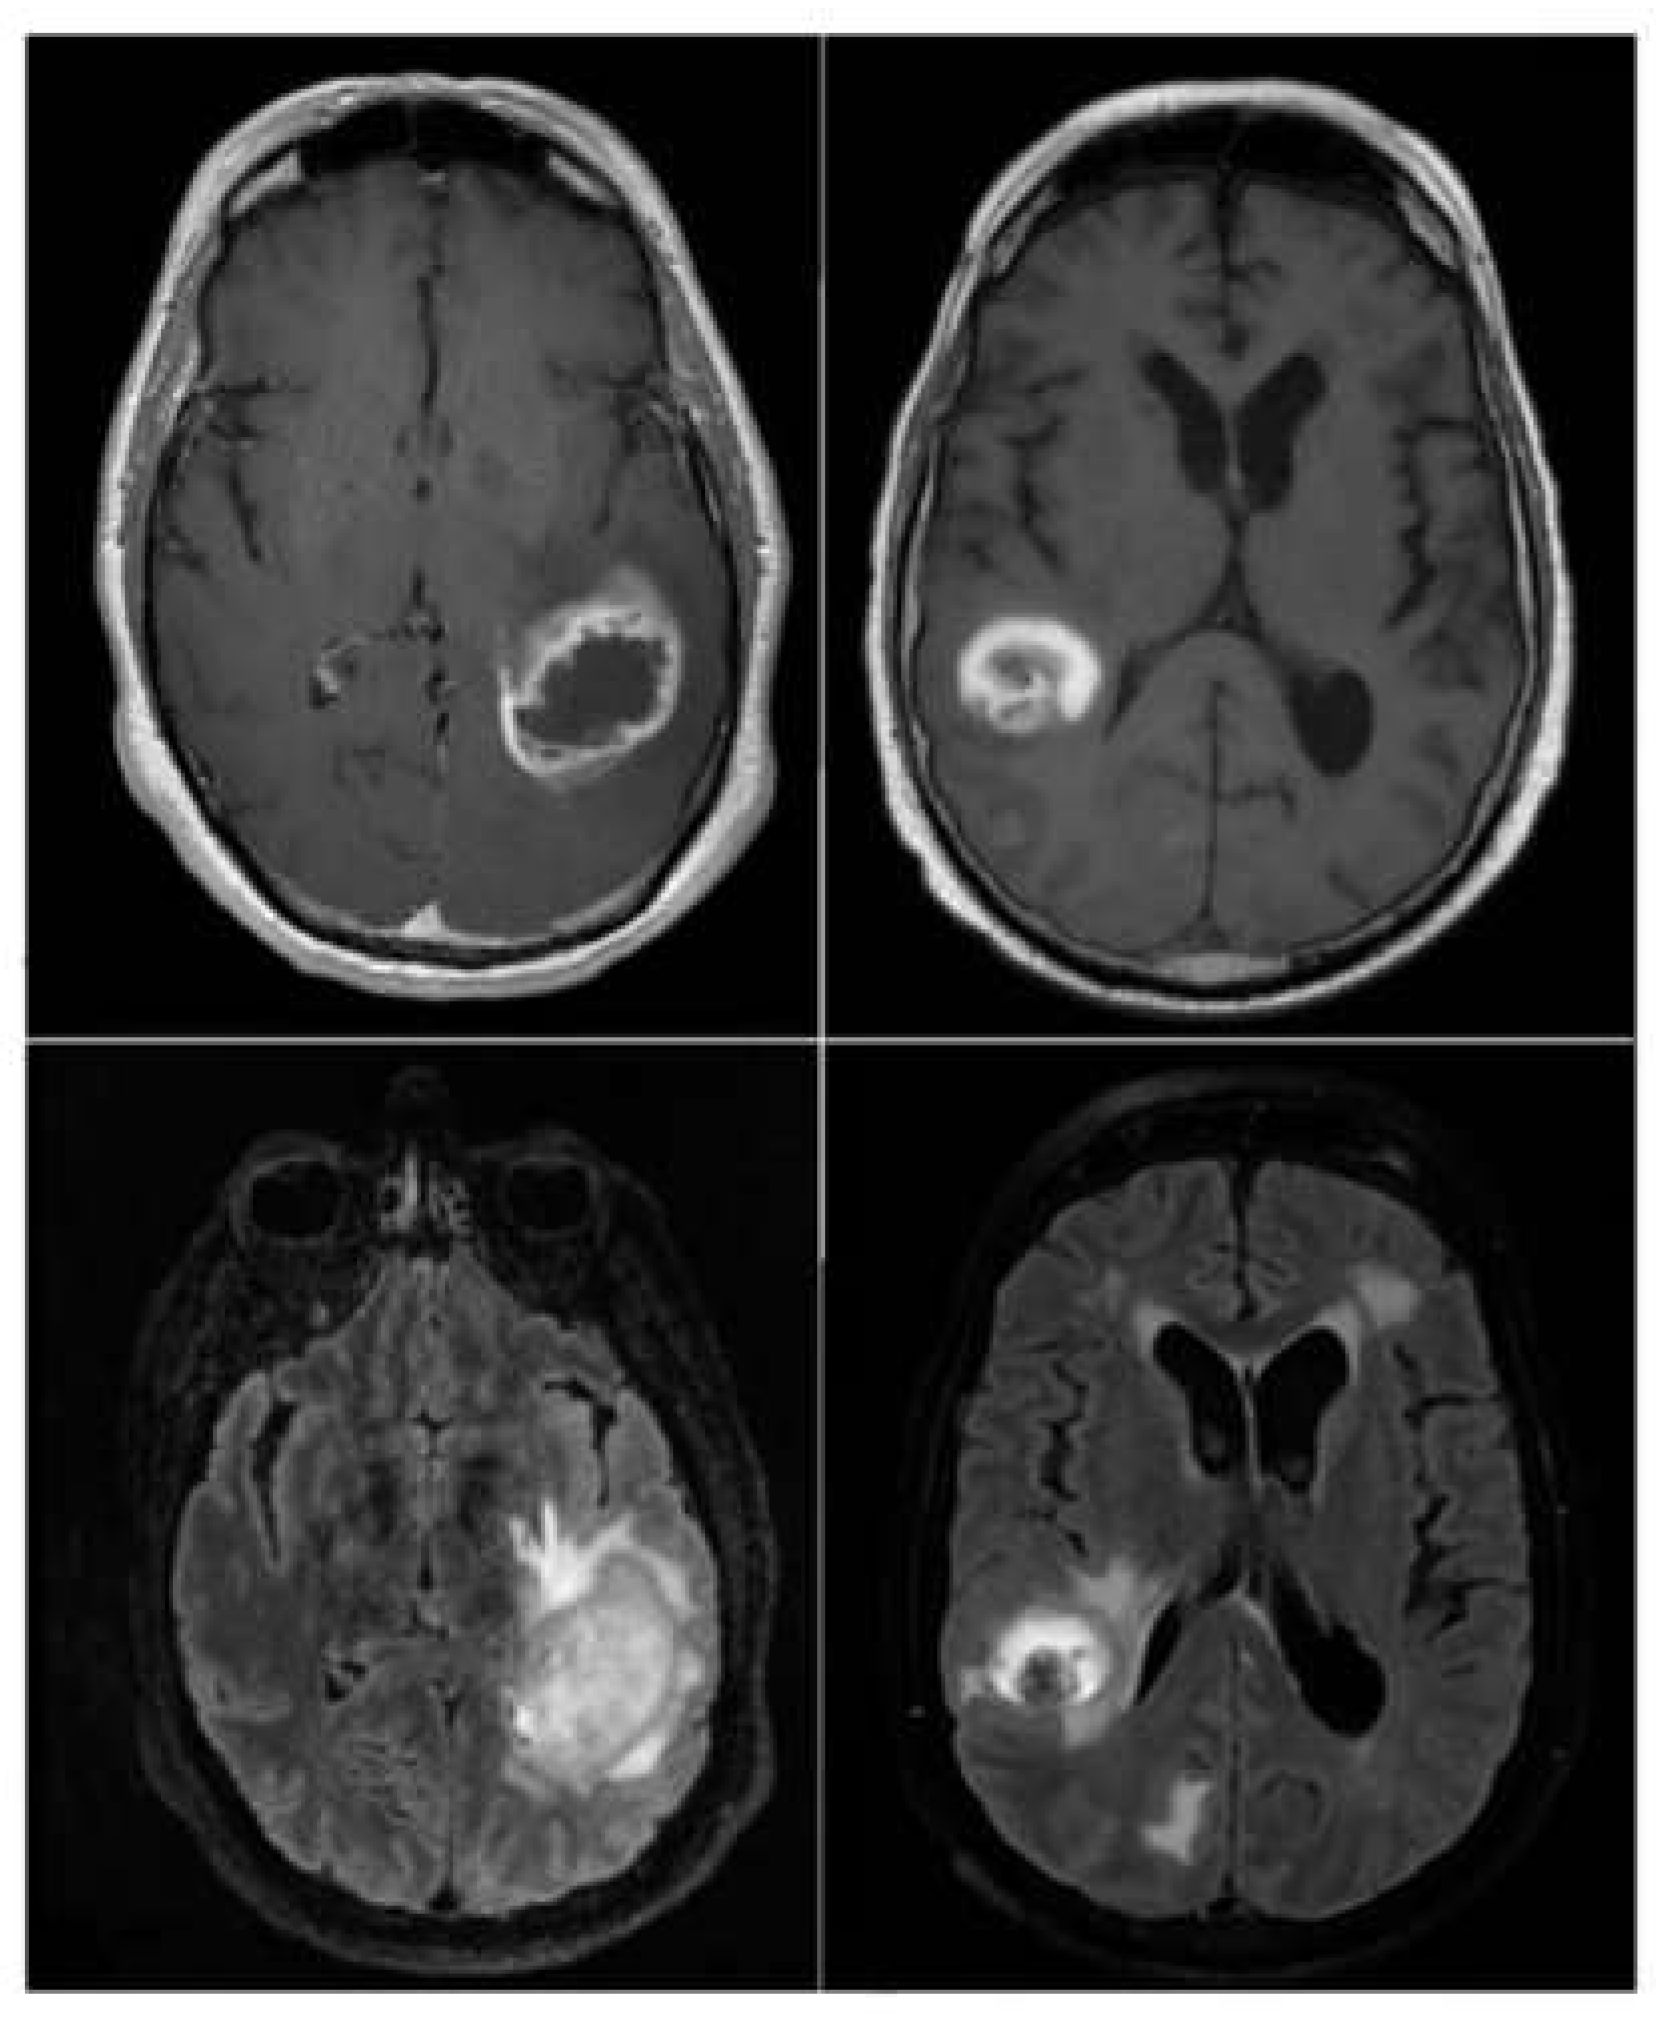

The Vision Transformer (ViT) model demonstrated the ability to focus on key tumor-related features, as shown by the attention maps in Figure 7. In the MRI images, distinct tumor regions are visible, characterized by altered enhancement patterns and edema surrounding the lesion. The corresponding attention maps reveal that the model consistently highlights patches associated with these abnormal regions.

The attention maps indicate that the model assigns higher attention (marked by warmer colors like red and yellow) to areas likely containing tumor tissue, suggesting it recognizes significant pathological features. This interpretability reinforces the clinical relevance of the ViT model, as it not only distinguishes tumor areas effectively but also aligns its focus with known tumor characteristics, aiding in understanding the basis of its predictions. These examples illustrate the model's capacity to differentiate response patterns in brain metastasis, potentially contributing to improved diagnostic confidence in clinical settings.

Figure 7. MRI image (left) side – by –side with its corresponding attention map(right).